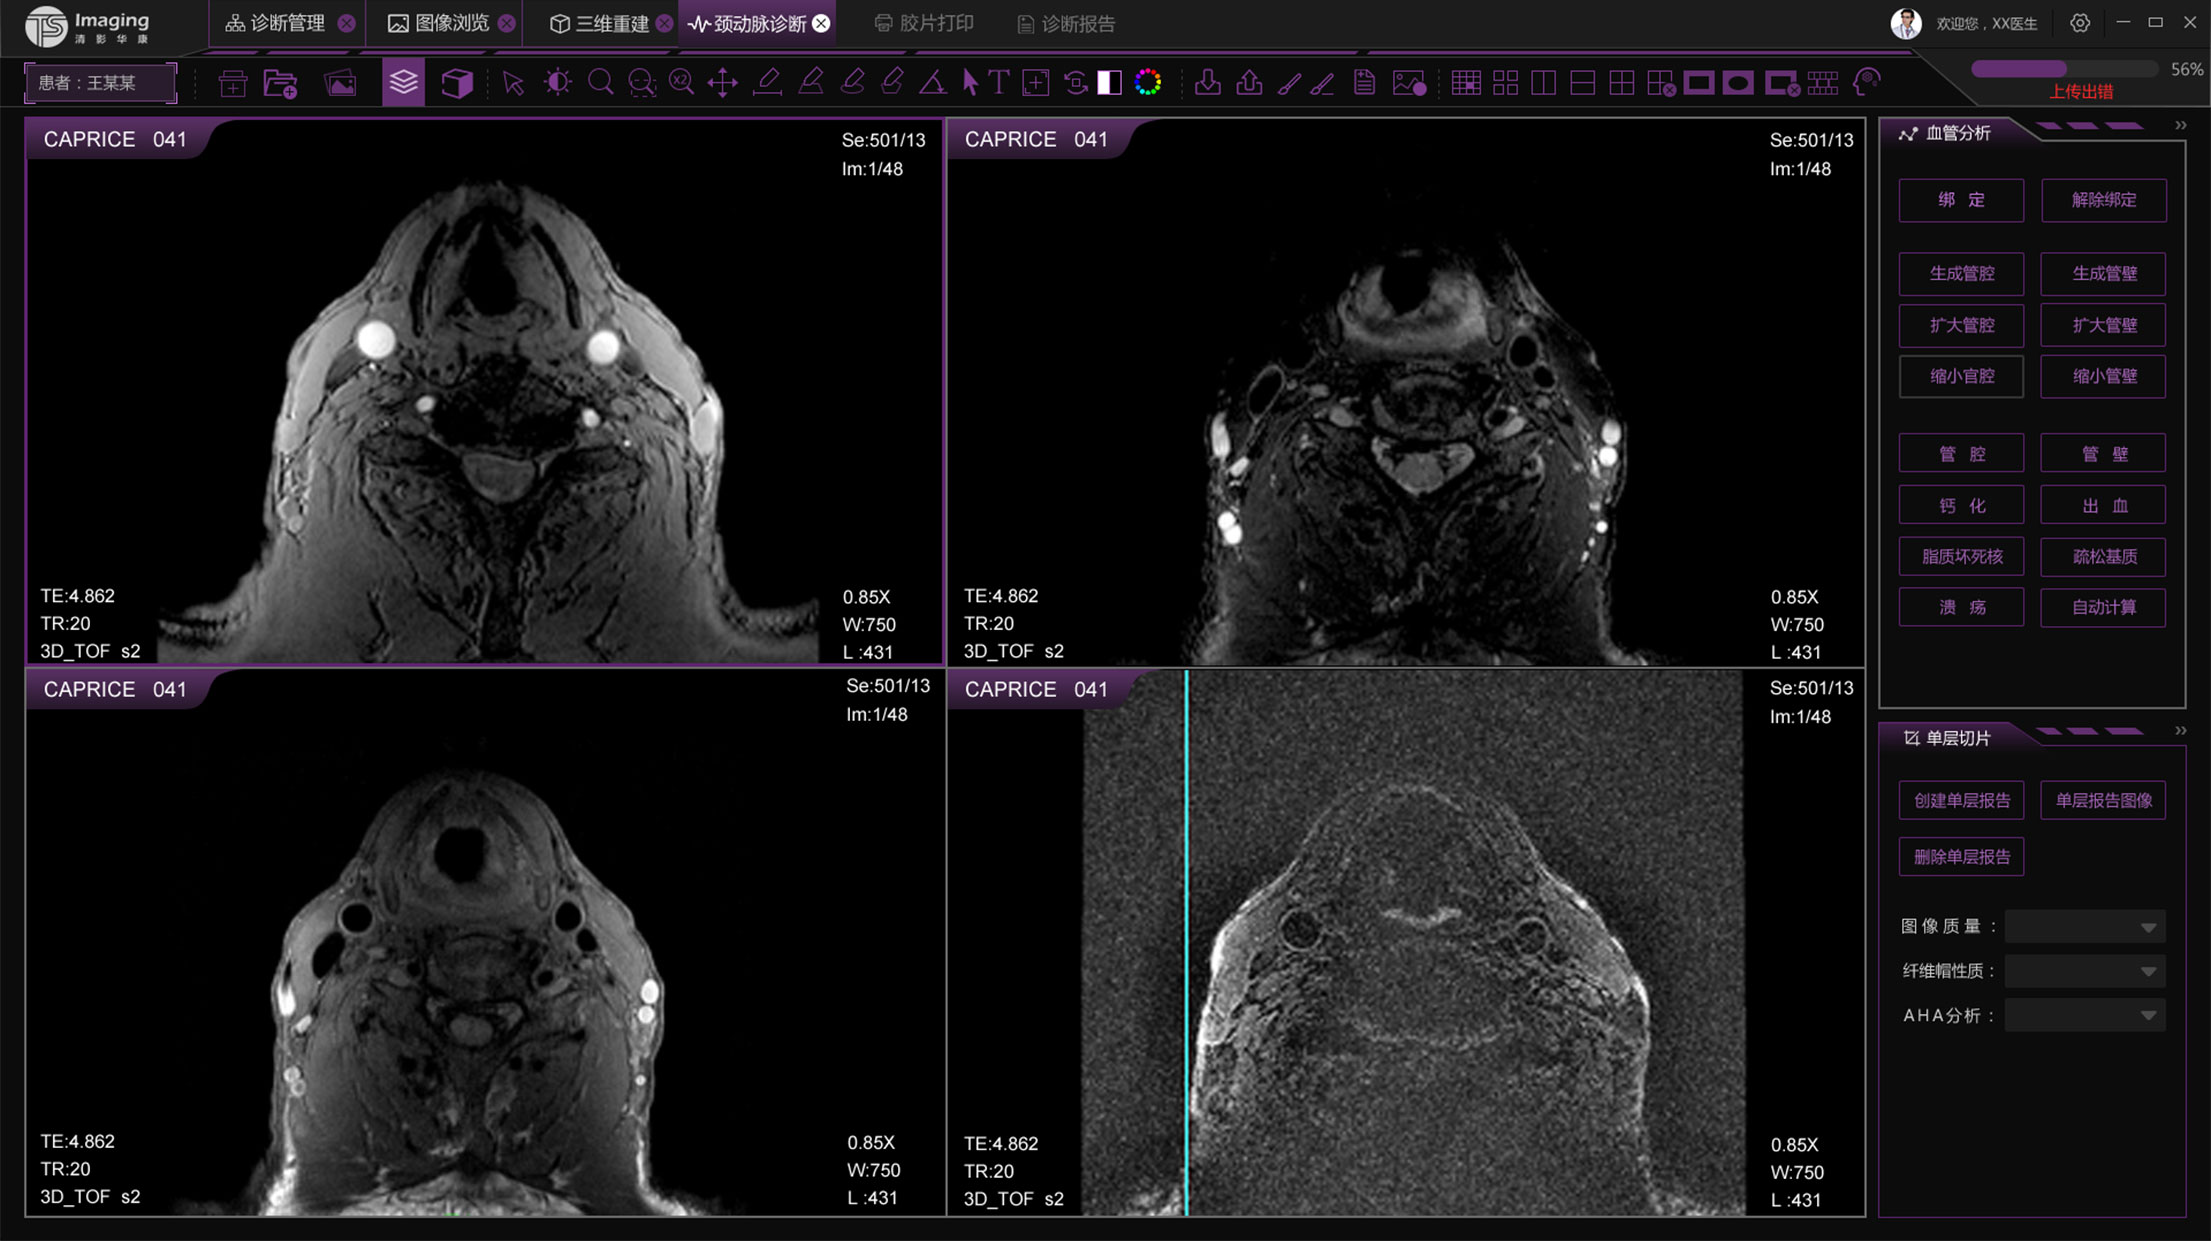

頸動(dòng)脈診斷頁面

頸動(dòng)脈診斷頁面整體布局和三維重建比較相似,最大的區(qū)別是右側(cè)的操作區(qū)域,血管分析都為按鍵操作,通過間隔的大小分成三部分。單層切片除了按鍵還有下拉菜單的操作。

頸動(dòng)脈診斷原型